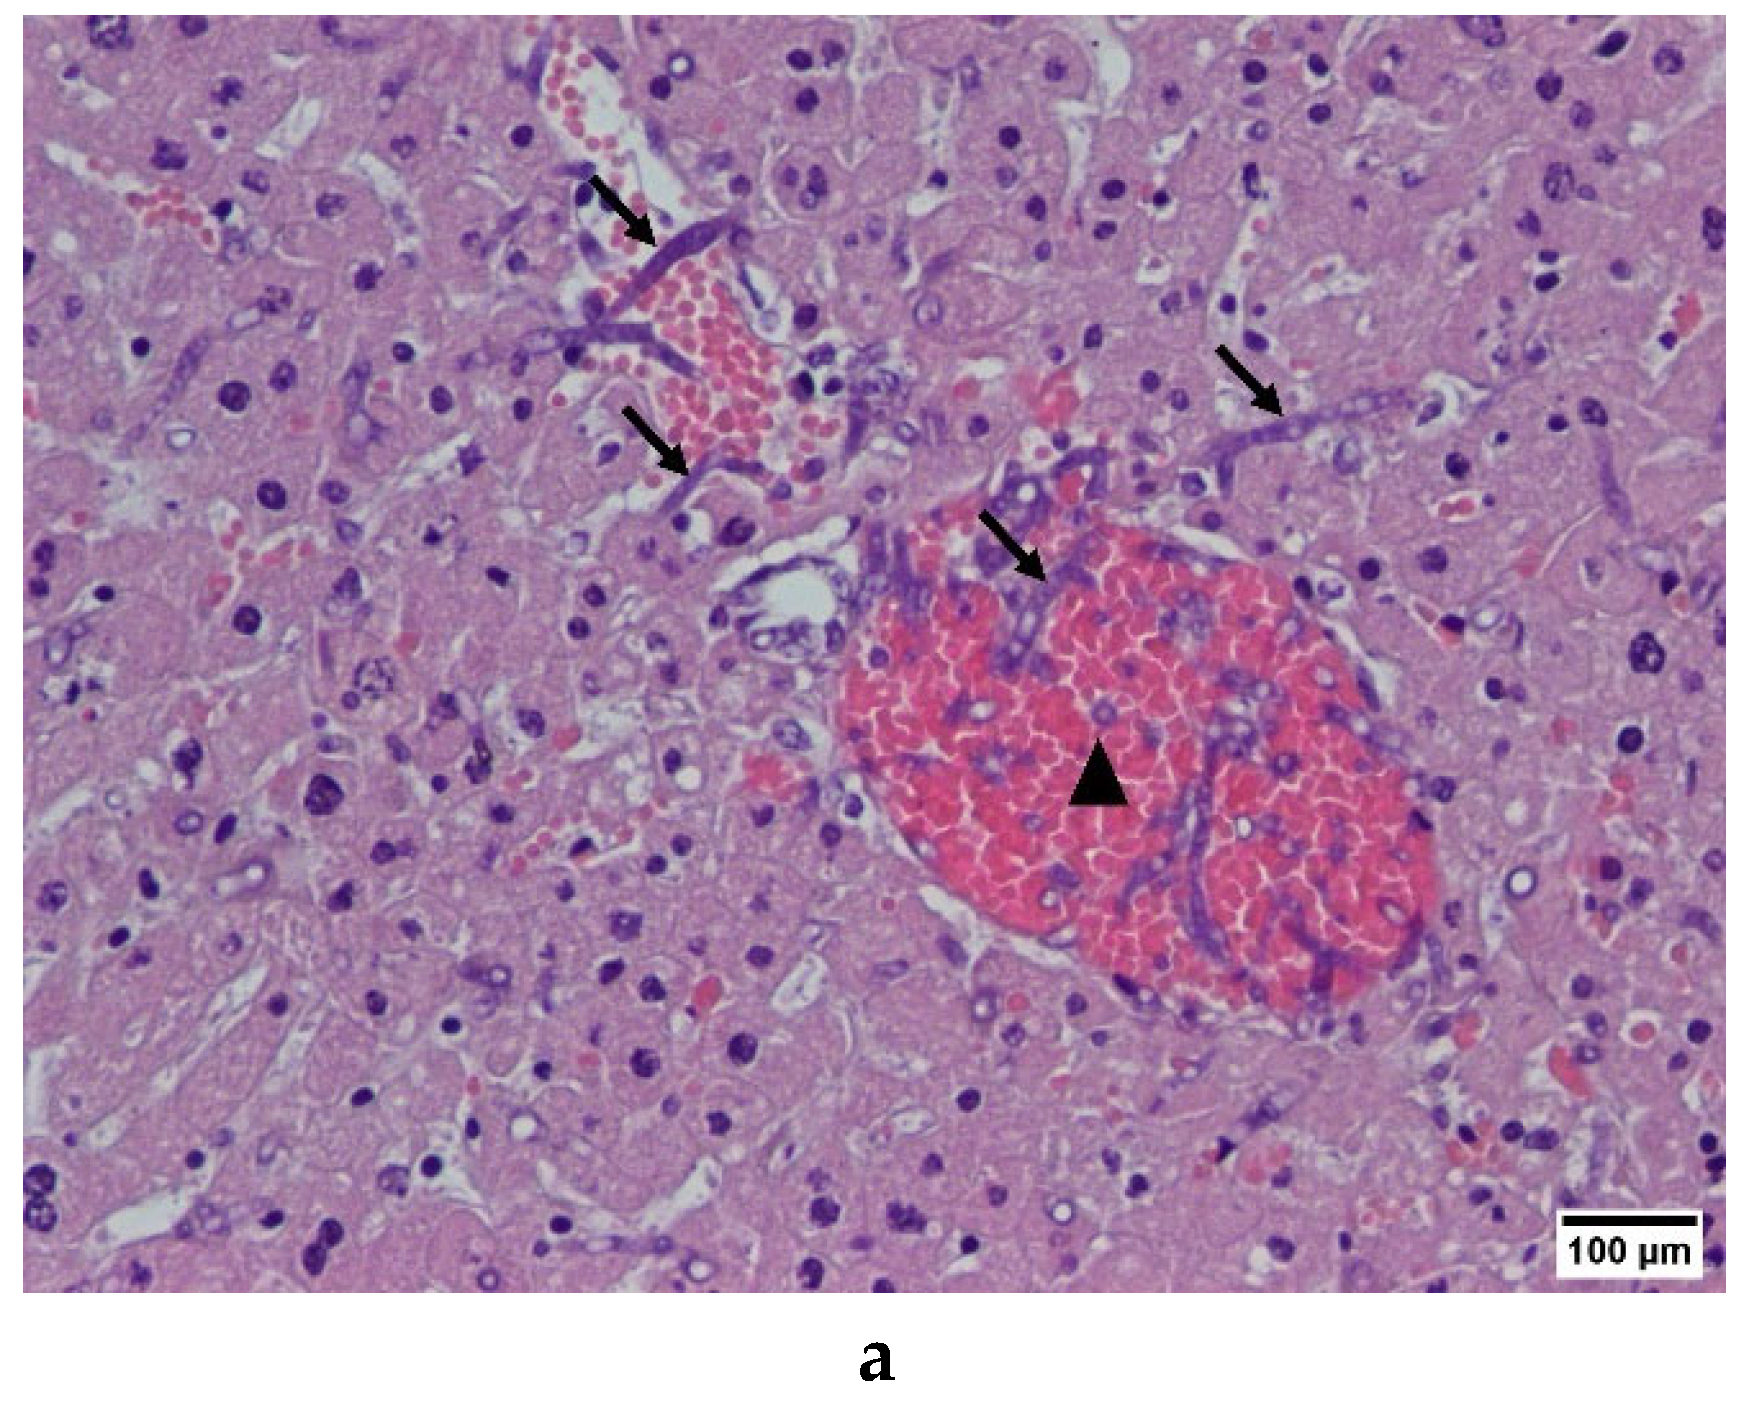

2.1.2. Immunofluorescence and Immunohistochemistry

4.10. Establishment of Invasive Aspergillosis Mouse Model